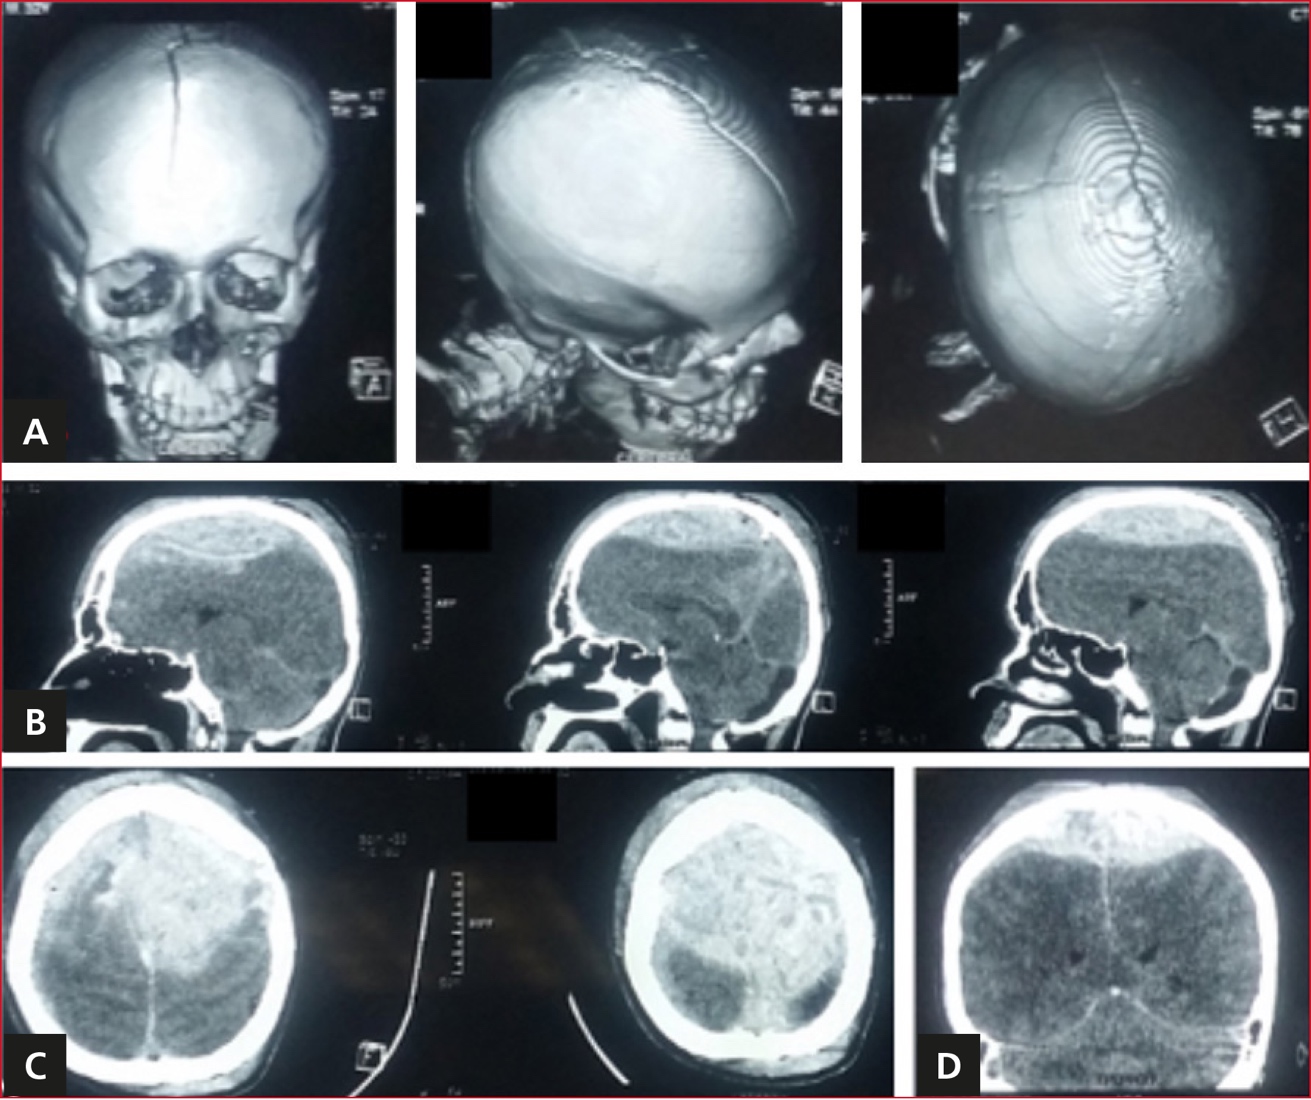

En la tomografía simple de cráneo inicial, se evidenció HEV, diástasis de sutura interparietal y hematoma subdural agudo derecho (Figura 1).

Figura 1. Tomografía computarizada simple de cráneo. Imágenes tomadas al ingreso del paciente. A. Reconstrucción ósea: diástasis traumática de sutura interparietal con fractura asociada a hundimiento y desplazamiento. B-D. Cortes sagital, axial y coronal, respectivamente. Imagen hiperdensa epidural biparietal, con efecto de masa, imagen hiperdensa subdural supratentorial derecha.